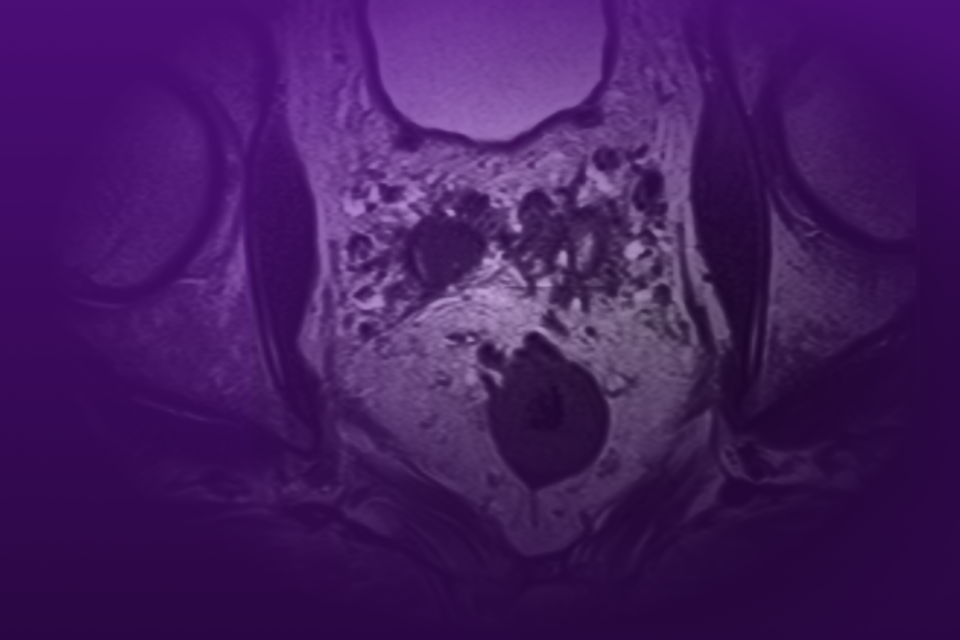

Robotic Management of Giant Hydronephrosis & Contralateral UPJ Obstruction

Dr. Brian W. Chao details his approach to robotic nephrectomy and pyeloplasty for incidentally discovered giant hydronephrosis and contralateral UPJ obstruction.